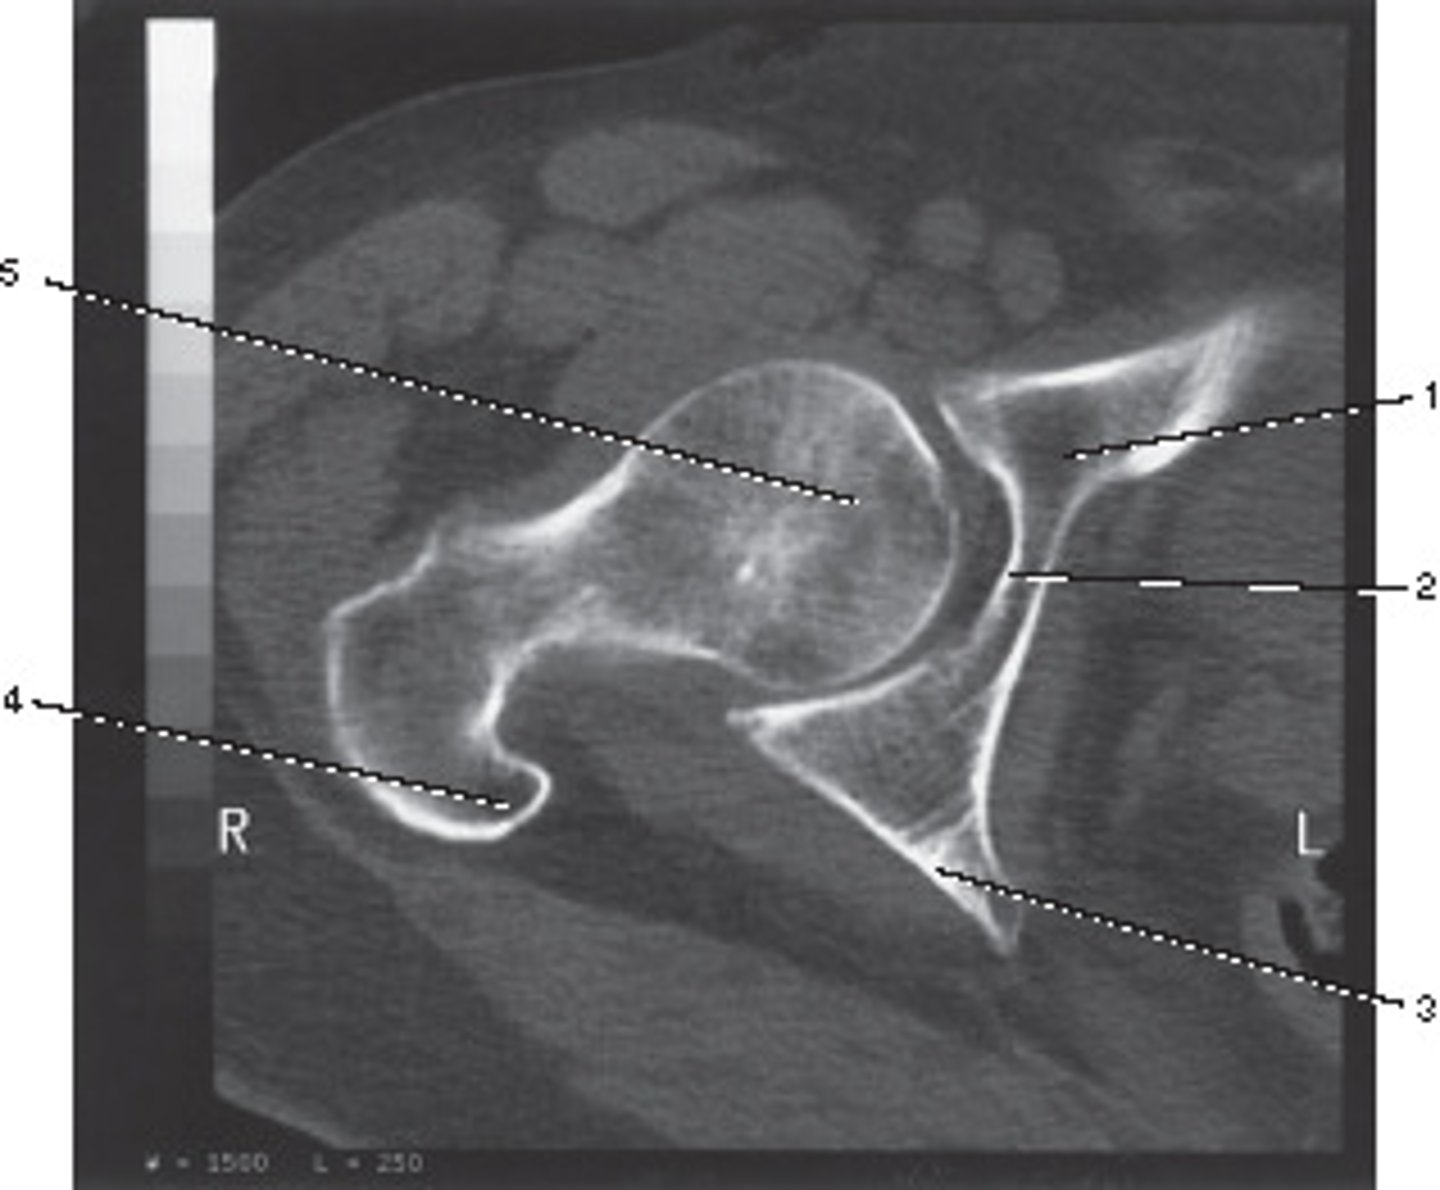

Fovea Capitis

<p>Number 1 corresponds to which of the following?</p>

What number corresponds to the acetabulum?

<p>What number corresponds to the acetabulum?</p>

Ilium

<p>Number 4 corresponds to which of the following?</p>

Coccyx